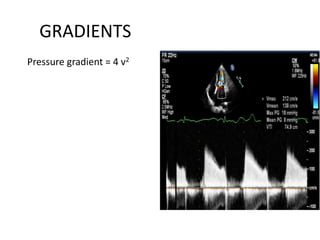

GRADIENTS

Pressure gradient = 4 v2

• Apical window

• CWD at or after tip of

mitral valve

• Maximal and mean

gradient

• Derived from

transmitral velocity

flow curve

• Heart rate to be

mentioned

• CD to identify mitral jet